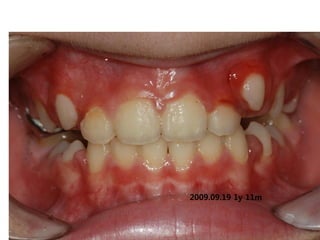

1999.05.26 /M

C.C

• Crooked teeth

Dx

• Lack of space caused by perioral muscle action

Goal

• Establish normal tongue posture and lip tone

with T4K

2009.09.19 1y 11m